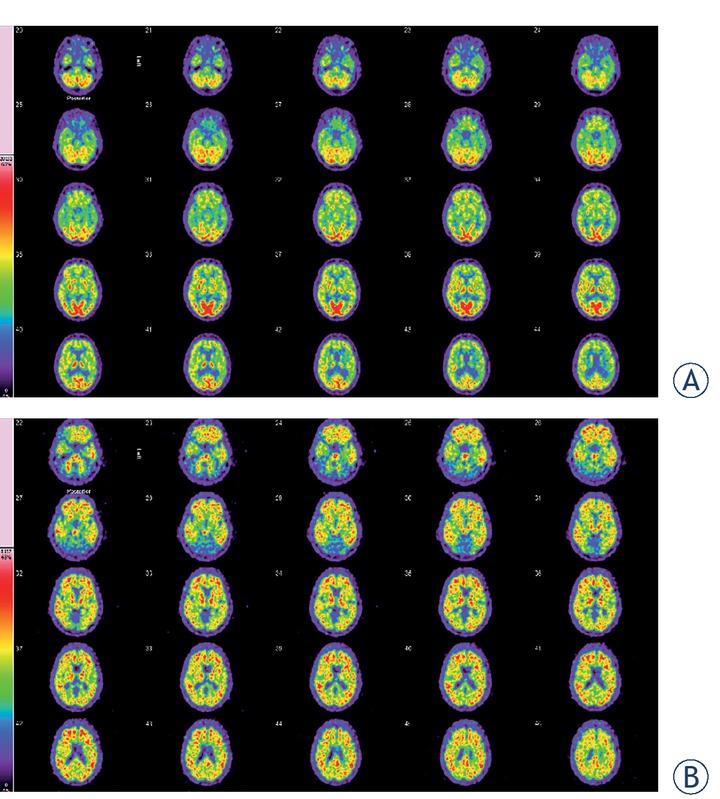

Figures 1 and 2 demonstrate FDG PET and amyloid positive PET images of patients with the clinical suspected diagnosis of AD.

2-[18F] fluoro-2-deoxy-d-glucose (FDG) and amyloid brain PET/CT of 59-year-old woman. (A) FDG brain PET/CT of a 59-year-old woman with a history of fluctuating cognitive impairment (mini mental state examination [MMSE] = 14/30). Glucose hypometabolism was demonstrated in the parietal dorsolateral and temporolateral, and occipatal cortical areas. The glucose metabolism in the left temporomesial area is weak. The other cortical structures show a slight attenuation of FDG metabolism. Basal ganglia show more intense uptake compared to the cortical areas. This FDG brain PET study shows the typical picture of abnormal glucose metabolism that occurs in Alzheimer´s disease (AD) and is additionally compatible with pronounced microvascular changes. (B) On the amyloid PET a non-specific tracer accumulation from the pons to the basal ganglia is evident. PET images of the white matter demonstrate individual non-specific enrichments. In the frontal and temporal cortices as well as sporadically in the parietal cortical areas, a pathological tracer accumulation occurs. This global cortical tracer uptake is consistent with the neuropathology of AD.